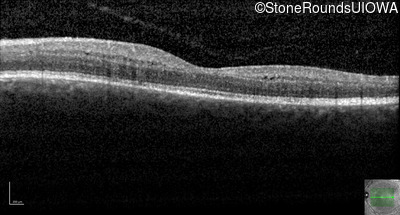

Optical Coherence Tomography - Right - 20/25 -1

Exemplar / OCT Stack